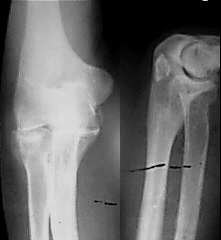

标题: X0660:请讨论尺骨鹰嘴处高密度影

男,30岁,右桡骨小头骨折两月复查

拍照时不用闪光灯,图象会更好,尺骨鹰嘴高密度影,是否骨岛?

见到这个高密度影,如果是我,我会针对这个高密影照其切线位片进行观察,建议楼主照其切线位片!!!

看是游离的,或是尺骨本身上的,如果是游离的,则可以考虑是撕脱性骨折。

桡骨小头骨折,尺骨鹰嘴可疑骨岛

如果,术前没有,,,,,,,,,,复查时发现的,那就是缺血所至了______无菌坏死与骨岛鉴别!!

考虑骨梗死可能性大

正位片不清且未包全软组织,病人有外伤史,应先排除异物。

考虑1股梗死。2骨岛。3骨化性肌炎。

当时骨折的片子如没有此阴影,考虑骨梗死可能性大